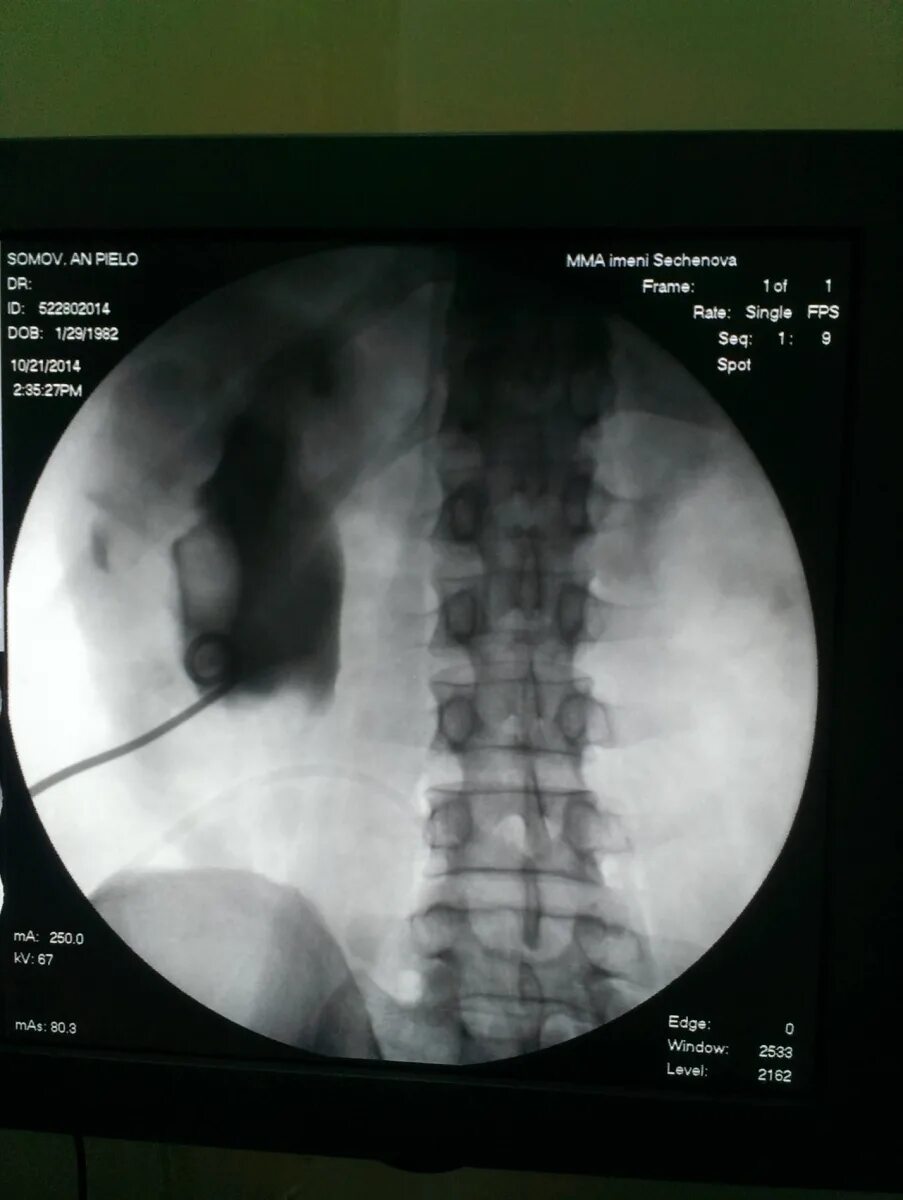

Гидронефроз почки после операции